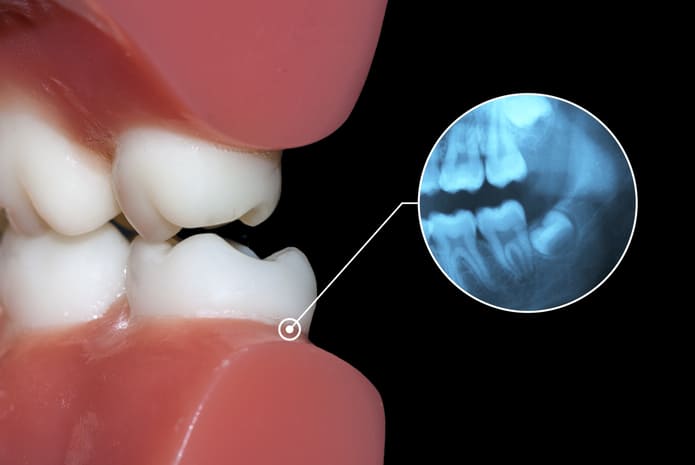

Si tu muela está retenida, puede estarlo de dos maneras.

- Retención parcial: Solo puedes ver una parte de la corona, ya que al intentar salir, no ha encontrado sitio suficiente y se ha quedado “a medias”.

- Retención total: Ni siquiera llega a atravesar la encía, por lo que no la podrás ver.

En cualquiera de los dos casos, lo que habrá pasado es que la muela del juicio ha crecido en ángulo contra el segundo molar que tiene al lado; o contra la parte posterior de la boca; o ha crecido hacia arriba como cualquier otra muela, pero nunca ha llegado a salir del maxilar.